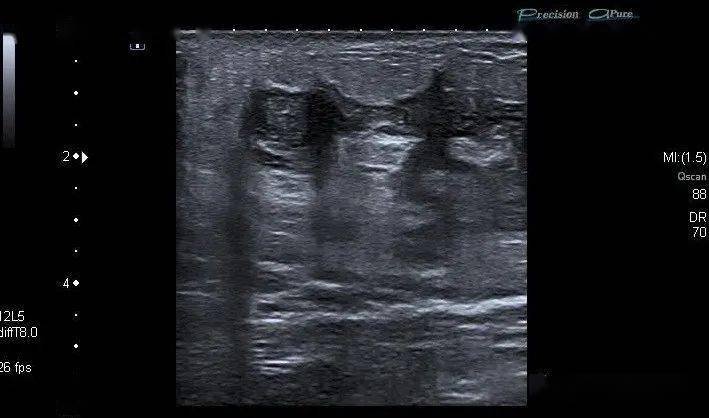

乳腺炎超声

发一张乳腺彩超,请各位医生们看看 - 超声医学讨论版 - 爱爱医医学